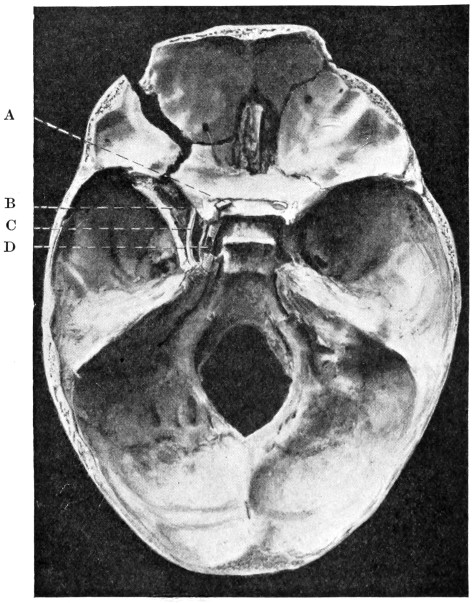

| 50 A and B. The inner aspect of the skull and the same seen on transillumination | 137 |

| 53. A basic fracture with laceration of both carotid arteries | 148 |

| 54. A basic fracture with laceration of the cavernous sinus | 149 |

| 55. A basic fracture with laceration of both lateral sinuses | 151 |